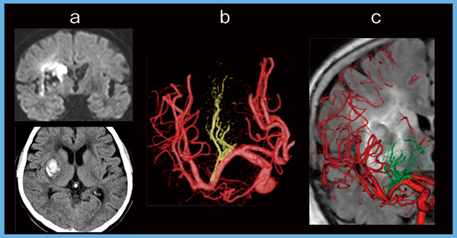

5.外側線条体動脈(lateral lenticulostriate artery:LSA)

LSAは中大脳動脈のM1〜M2 segmentから起始し,尾状核や被殻(外側),淡蒼球(内側),内包後脚の一部を灌流する重要な動脈である。LSAは終動脈のため副次的な血液供給は望めず,閉塞により容易に灌流領域に梗塞を生じる。高血圧の影響も受けやすく,特に最外側枝はCharcot脳卒中動脈と呼ばれ,高血圧での外側型被殻出血の原因となる。LSAも起始部と本数,分岐形態にバリエーションがあり,分岐部は動脈瘤の好発部位でもあるため,動脈瘤術前にLSAを同定することは重要である。

図7に,右被殻出血後の脳梗塞症例を示す。血腫の頭側に梗塞を合併している(図7 a)。LSAと血腫,梗塞の位置関係把握目的で施行したAquilion PrecisionのCTAで,LSAはM1/M2 junctionから起始し,その後複数に枝分かれするタイプであることがわかる。外側のLSAは保たれているが,内側のLSAが途絶している(図7 b)。MRIのFLAIR像とのフュージョン画像(図7 c)で,LSAの途絶部分は血腫の部位に一致し,この頭側に梗塞巣が広がっていることがわかり,血腫によるLSA閉塞が梗塞の原因であると考えられた。

図7 LSA,出血,梗塞の位置関係の評価